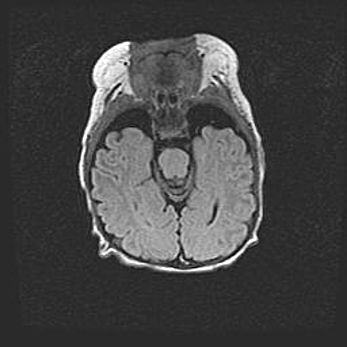

Сообщающаяся гидроцефалия. Кистозная энцефаломаляция головного мозга.

Возраст: 3 месяца 4 дня

Вес: 3100 г

Пол: женский

Окружность головы: 34 см

Срок гестации: 31 неделя

Кистозная энцефаломаляция головного мозга - одна из форм поражения головного мозга в детском возрасте. Характеризуется возникновением множественных и распространённых кист в коре, белом веществе и подкорковых образованиях головного мозга у плодов, новорождённых и детей раннего возраста. Развитие кистозной энцефаломаляции связано с внутриутробной асфиксией и гипотонией, родовой травмой, тромбозом синусов, пороками развития сосудов, инфекциями, сепсисом и другими причинами. Наиболее значимые инфекционные агенты: вирусы простого герпеса, цитомегалии, краснухи, токсоплазмы, энтеробактерии, золотистый стафилококк и другие.